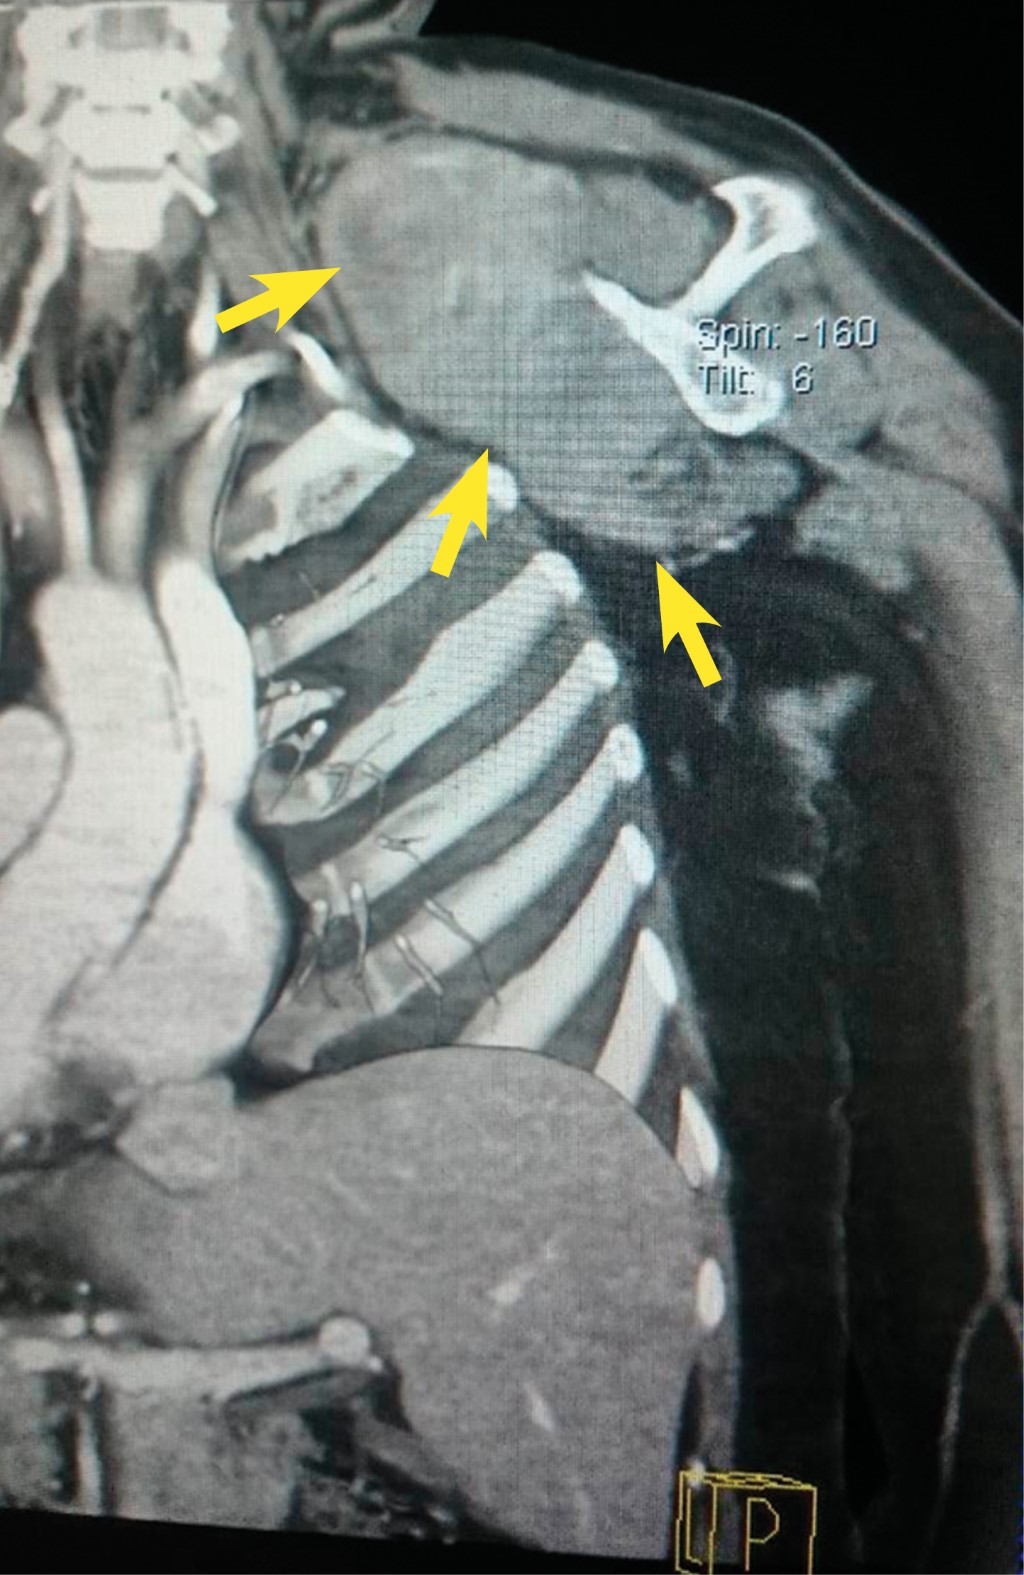

Por dolor postoperatorio se envió a la paciente a radioterapia, posterior a RMN, donde se encuentra lesión subescapular con extensión hacia la fosa supraclavicular, que involucra los músculos subescapulares. No se establece con certeza si es tumor graso o no, ni si tiene o no extensión intratorácica, por lo que se realiza tomografía computarizada que muestra un tumor subescapular derecho heterogéneo con tamaño de 11.6 × 11.5 × 9.4 cm, con aumento en su vascularidad, que comprime y desplaza la yugular interna, no erosiona la parrilla costal, erosiona la espina escapular, sin adenopatías, involucra el músculo subescapular y lo reemplaza en su totalidad (Figuras 1 y 2). Se observa paquete neurovascular axilar y supraclavicular respetado. Se hace biopsia percutánea en mayo de 2015 con RHP de miofibromatosis.